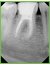

Zusätzliche Anatomie